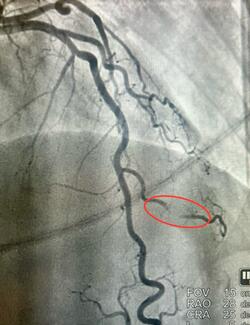

A 73-year-old man presented with exertional angina and anterior ischemia on stress testing. He had undergone prior coronary artery bypass surgery and multiple percutaneous coronary interventions.